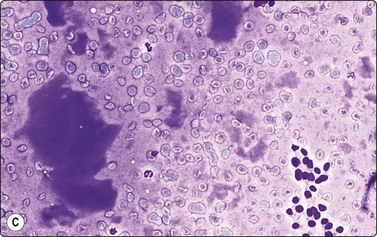

Smears in poorly differentiated thyroid carcinomas are hypercellular with single cells as well as cells in solid, trabecular and insular patterns. There is marked crowding of cells and tumor cells show high nuclear cytoplasmic ratios (Fig. 6.28).158

image image image

Fig. 6.28 Poorly differentiated carcinoma

(A,B) Smears showing syncytial clusters of crowded small cells with hyperchromatic nuclei (A, MGG, HP; B, Pap, HP); (C) Tissue section, same case. (H&E, IP).